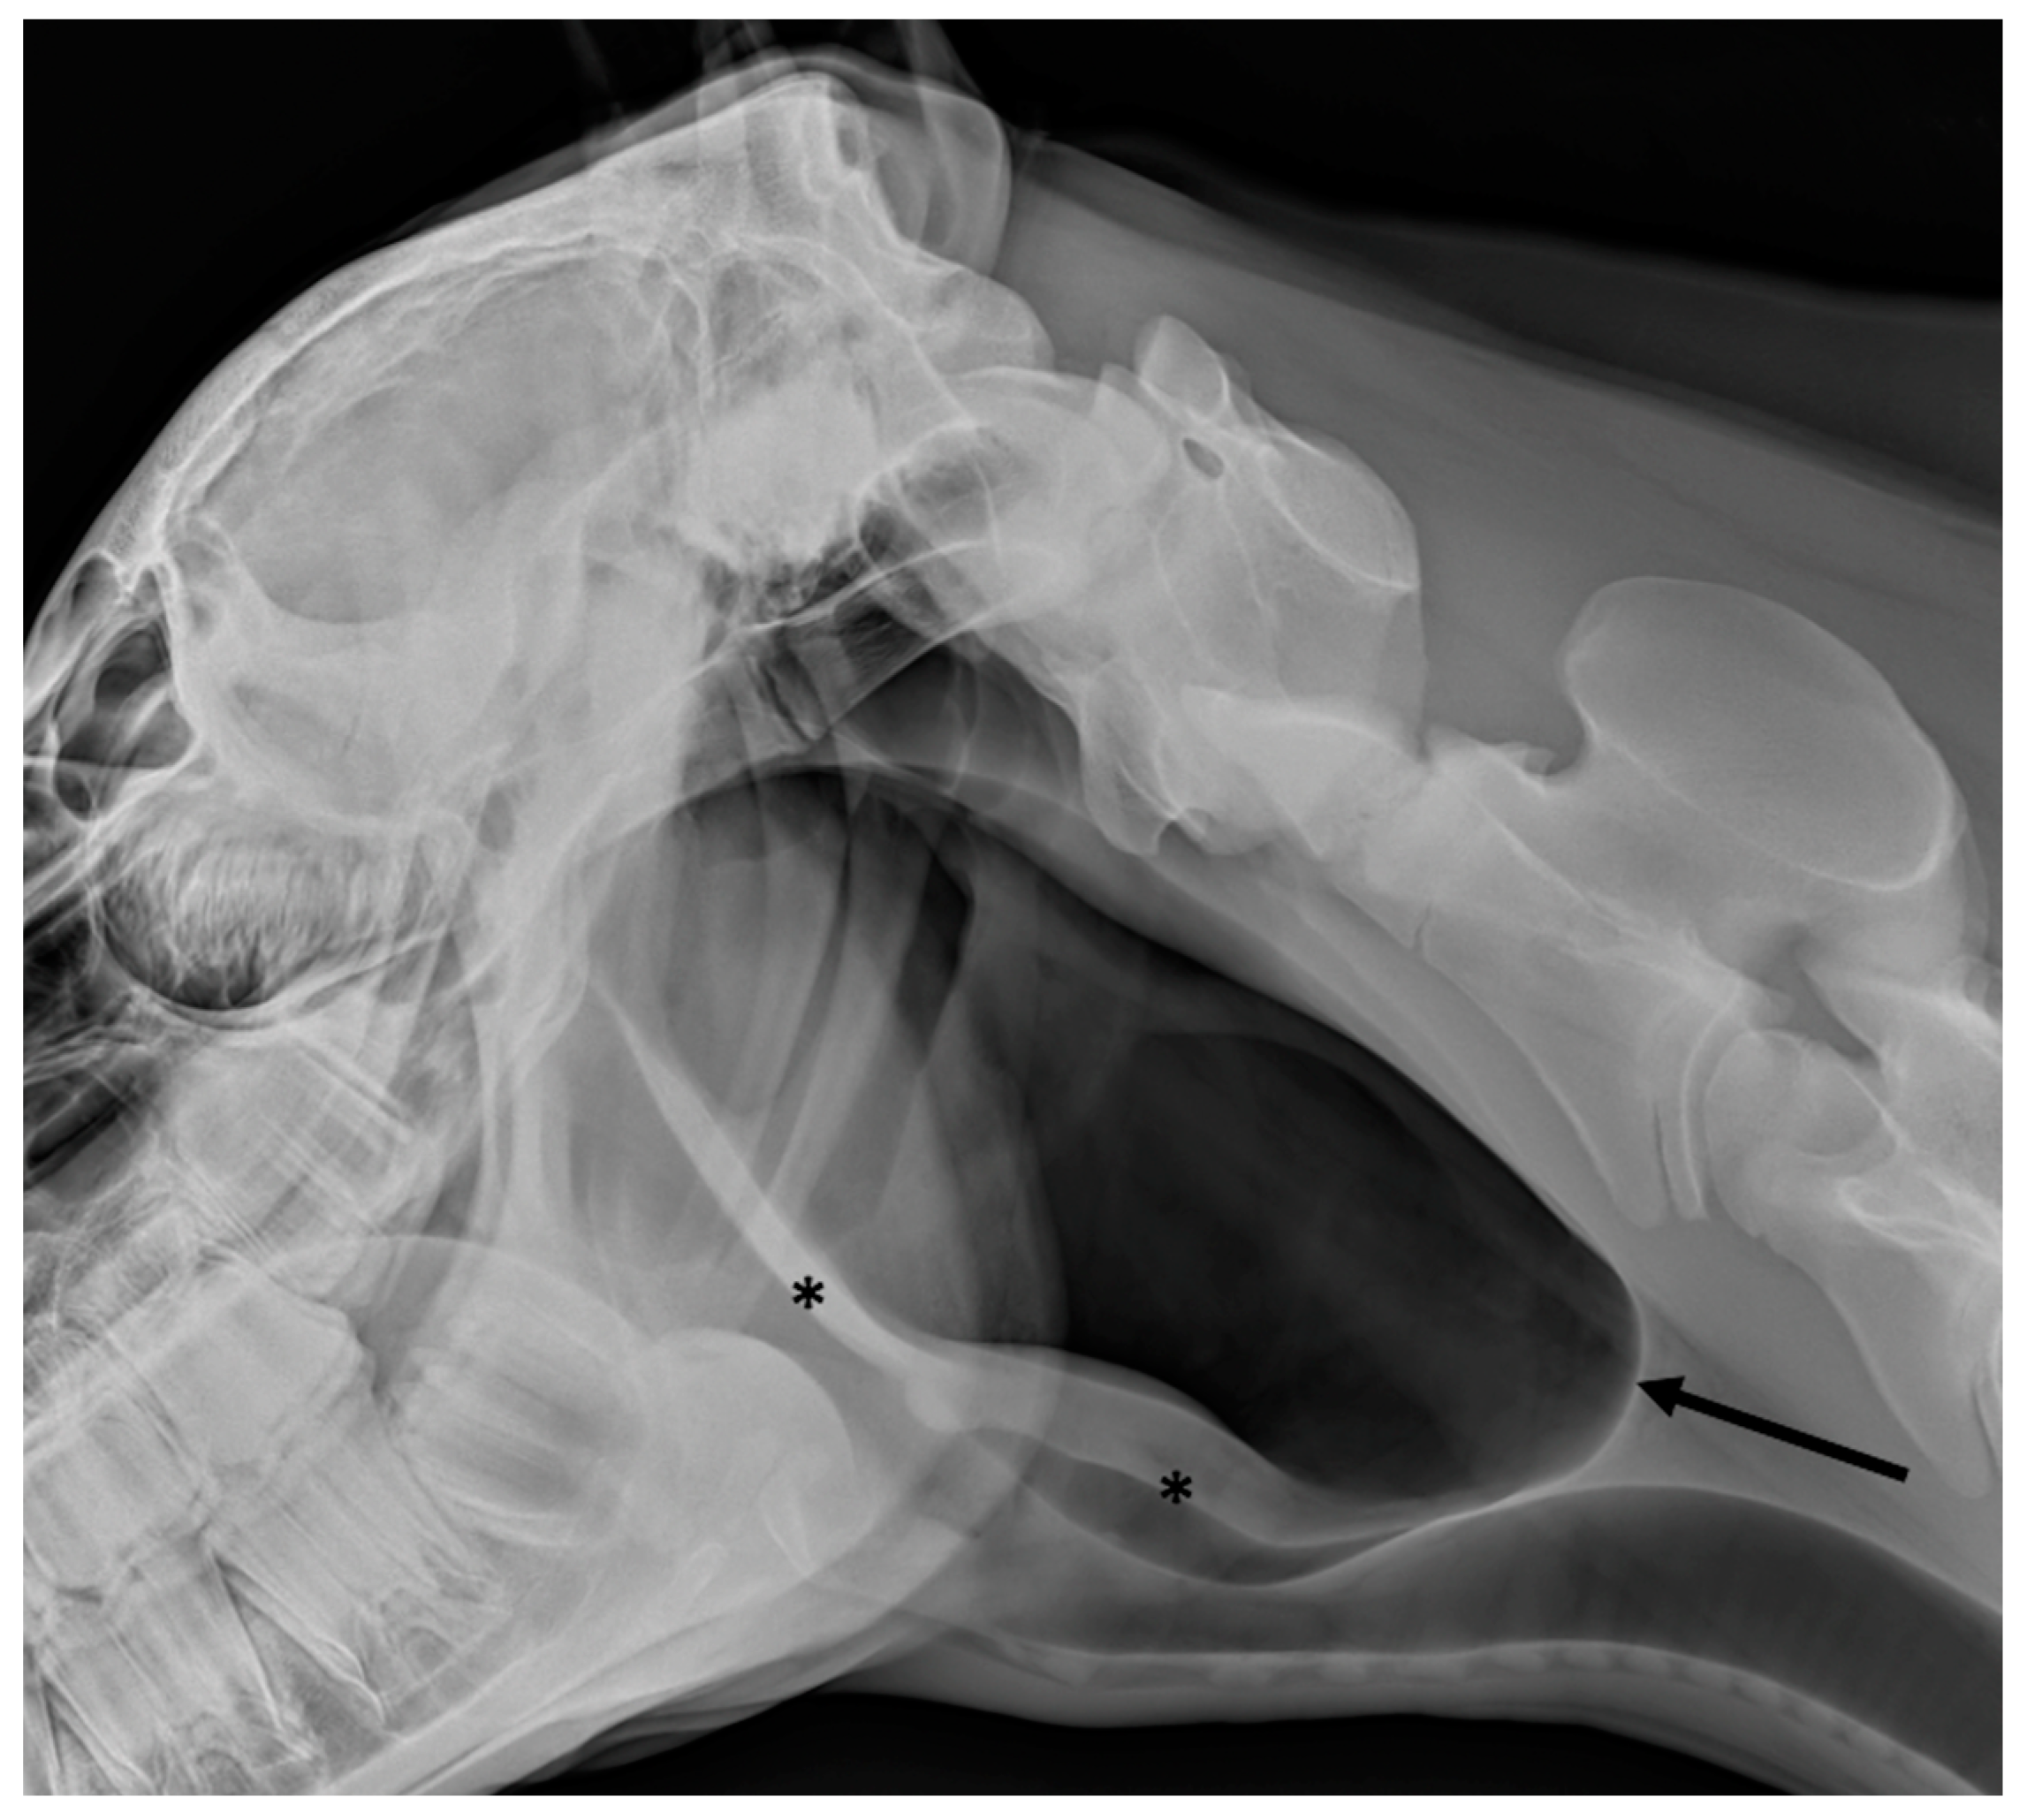

2.1. Radiography

3.4. Temporohyoid Osteoarthropathy